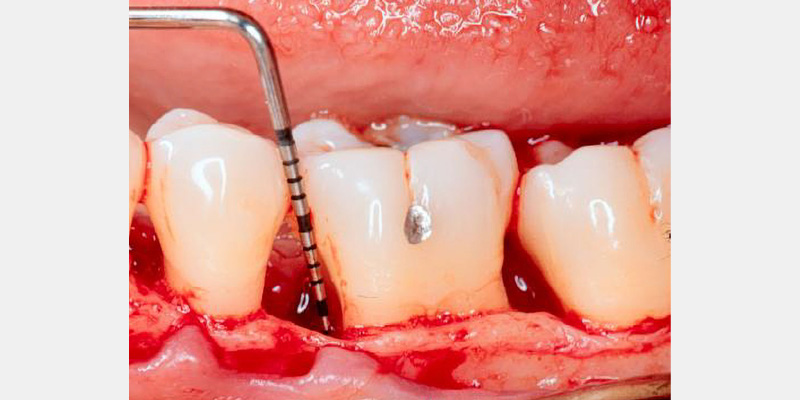

Periodontal regeneration includes the recreating of periodontal ligament, cementum and alveolar bone along the previously diseased and denuded root surface. The evidence supporting guided tissue regeneration is vast and growing. For decades dental surgeons have been using, with high levels of predictability, resorbable and non-resorbable barrier membranes in passive tissue engineering around teeth and dental implant dehiscence and fenestrations.3, 4 By employing active tissue engineering, new levels of predictability and success can be reached to resolve hard and soft tissue, periodontal and other orofacial defects.

Periodontal defects include the intrabony and furcation-type defects, as well as with gingival recession or loss of attachment. The periodontal literature validates the regenerative potential of biologically active bone replacement grafts (Figs. 1–5).5, 6, 7 Periodontal regeneration with histological evidence of new cementum, periodontal ligament and alveolar bone has been shown in the human model with a recombinant growth factor and a porcine (pig)-derived protein.8, 9, 10

The ability to reconstruct the tissues in an area that was previously infected by periodontitis serves as the ultimate acid test for regenerative achievement. Human recombinant platelet-derived growth factor (PDGF-BB), a protein that regulates cell growth and division, and beta tricalcium phosphate (β-TCP), a drug delivery system for bone, have been shown to accelerate clinical attachment level gains and significantly increase bone growth in severe periodontal defects.11 Recombinant human platelet-derived growth factor (rhPDGF-BB) and enamel matrix derivative (EMD) have demonstrated tissue regeneration when used adjacent to a previously diseased root surface.8, 9, 10

Histologic evidence from a recent study shows that regeneration can be achieved with rhPDGF-BB, β-TCP, and collagen in gingival recession-type defects.12 Gingival recession defects have been treated successfully with rhPDGF, β-TCP and a collagen membrane with a root coverage technique (Figures 6–7). This technique was compared to a subepithelial connective tissue graft within a case series,13 and more recently in a controlled clinical trial. The comparisons demonstrated that the growth factor technique was comparable to the others for root coverage outcomes.14 Many studies validate the use of EMD for periodontal and mucogingival defects.5, 6, 15 The histological article on EMD offers proof of principle for incredible quantities of true periodontal regeneration.16